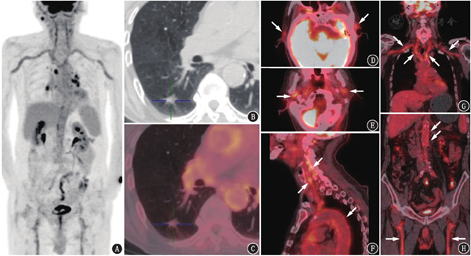

18F-FDG PET/CT图像见右肺下叶背段不规则实性结节,直径约1.1 cm,边缘毛糙,未见代谢活性,考虑可能为良性结节(图1)。此外,意外发现主动脉(升主动脉、主动脉弓、降主动脉、腹主动脉)、双侧胸廓内动脉、头臂干、双侧锁骨下动脉、双侧颈总动脉、颈外动脉、上颌动脉、颞浅动脉、双侧椎动脉、双侧髂总动脉及双侧股动脉管壁代谢弥漫增高(图1),SUVmax 5.2,血管壁代谢增高区呈连续、环周分布,尤其是头颈部各分支。PET/CT诊断:结合大血管典型受累部位及范围考虑,大动脉炎可能性大;患者病史中有视野缺损及视力下降,双侧颞下颌关节处在咀嚼时有疼痛,考虑与其供血动脉(颞动脉及上颌动脉)受累相关。临床最终诊断为巨细胞动脉炎,予泼尼松、环磷酰胺治疗后,眼部症状较前好转,缺损范围较前缩小,颞下颌关节处疼痛较前减轻,ESR降至7 mm/1 h,CRP降至0.83 mg/L。